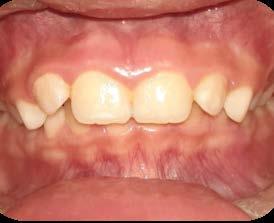

Entre los elementos que conforman al sistema estomatognático, están los dientes caninos, órganos dentales esenciales en la fisiología masticatoria; punto de unión y continuidad estética entre la línea de la sonrisa y el corredor posterior del arco dental, además de que ejercen la función de pilares estabilizadores en la oclusión fisiológica (Figura 1).

Los caninos son indispensables durante los movimientos de lateralidad y vitales para la continuidad de los arcos dentales, tanto en la dentición decidua como en la permanente; son responsables del funcionamiento y la armonía oclusal. Su posición adecuada en el arco asegura un buen contorno de la cara, sonrisa agradable y armónica con la estética facial. (Figura 2).